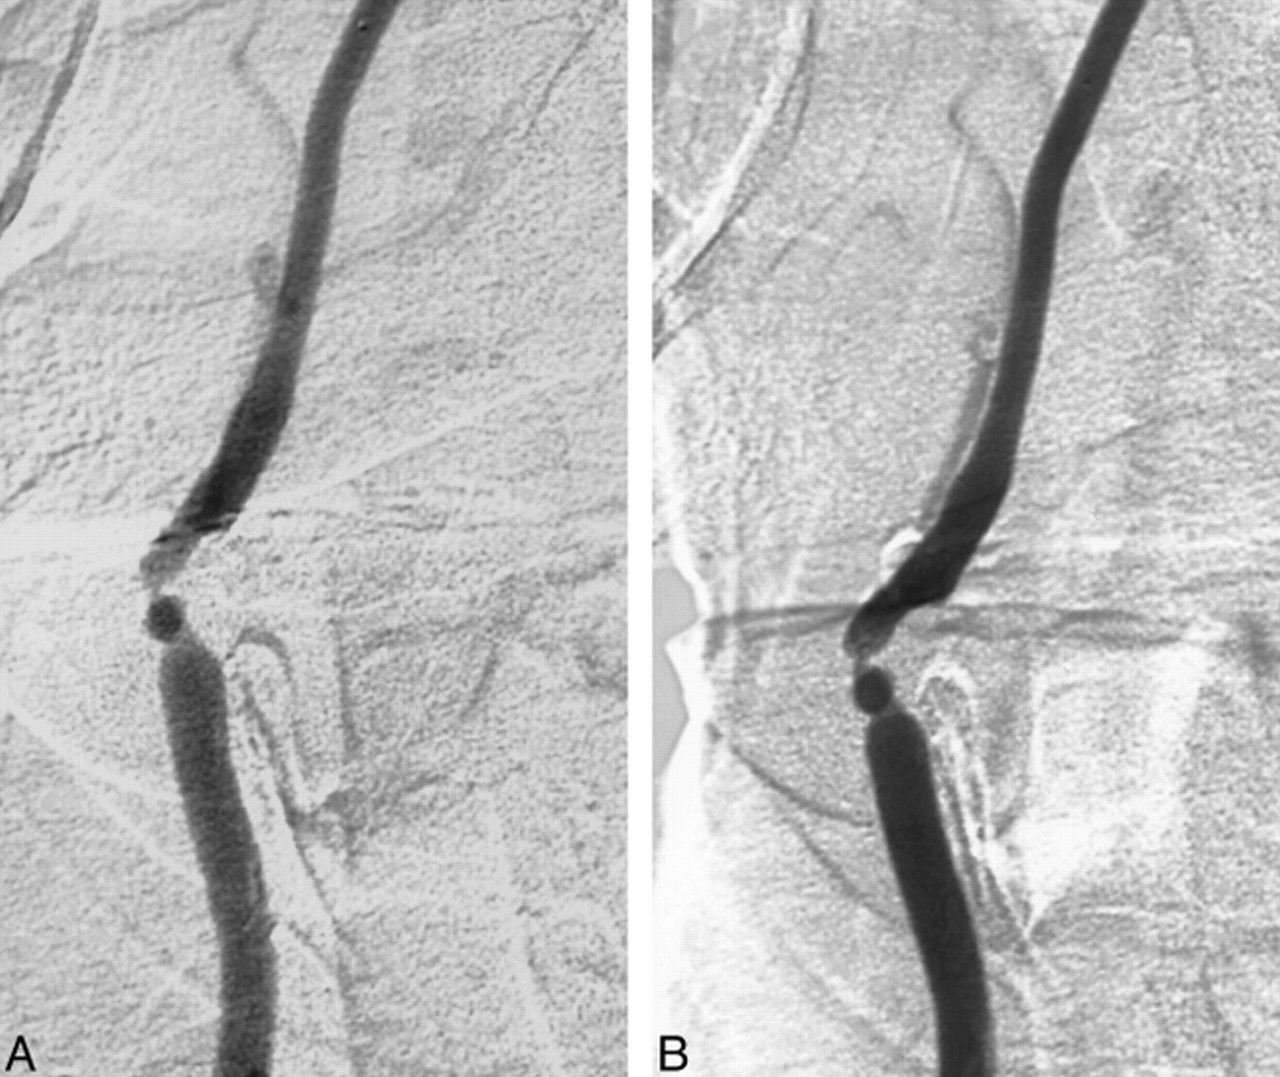

In this study, measurable carotid arterial stenosis was not significantly different between studies performed with gadopentetate dimeglumine and iohexol. However, the images obtained with the use of the gadolinium agent were judged to be of lower quality than those obtained with iohexol (Fig 3). Some of this difference may be attributed to the study design, in that if an iodine-based study was judged to be nondiagnostic, the examination was repeated. No repeat examinations were performed when the gadolinium-based contrast agent was used, even if the examination was clearly substandard. In practical application, cerebral arteriograms are reviewed as the examination is performed. If during the course of gadolinium-based carotid angiography there is doubt about the degree of stenosis, or if an arteriogram is judged to be nondiagnostic, additional injections can be performed. With our injection sequences, a total of 32 mL of gadopentetate dimeglumine was injected. Depending on the size of the patient, it may be possible to repeat all of the gadolinium injections without exceeding the commonly used dosage of 0.3 mmol/kg.

A and B, Gadolinium- (A) and iodine-based (B) frontal projections of common carotid arteriogram. Although the depiction of vascular anatomy is equivalent, there is relatively decreased intravascular contrast on the gadolinium examination